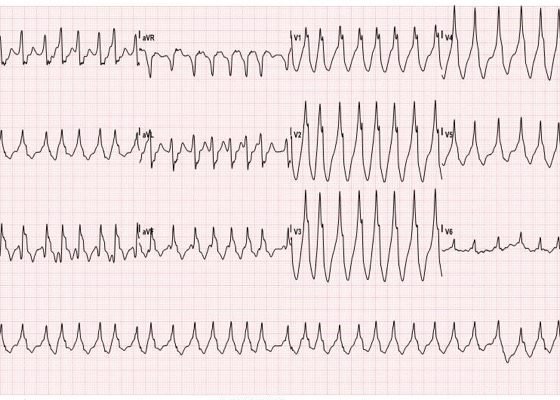

Wolff-Parkinson-White Syndrome: Electrocardiogram

DOI: https://doi.org/10.21980/J8201KThe initial EKG showed wide complex, irregular tachycardia > 200 bpm (EKG 1). Given the possibility of Wolff-Parkinson-White (WPW), procainamide was given to the patient. The patient’s heart rate responded and decreased to 120-140 bpm with narrowing of the QRS complex. A repeat EKG showed narrow complex tachycardia without P waves approximately 120 bpm (EKG 2). Once the procainamide infusion was complete, the patient had converted to sinus rhythm with a delta wave now apparent, consistent with WPW (EKG 3).